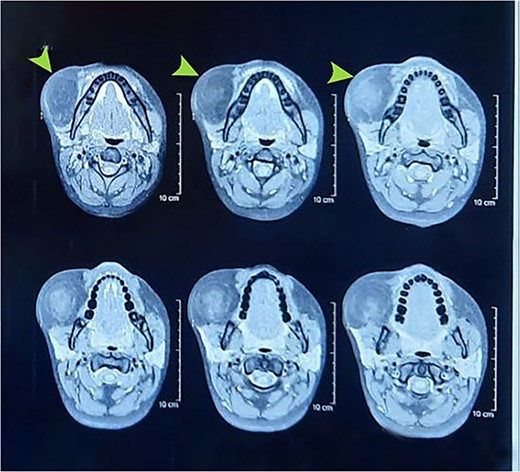

Laboratory investigations included a full blood count that revealed a slightly lower MCV, MCH, and MCHC with slightly elevated platelets. Other laboratory investigations, including lipid profiles and blood sugar levels, were normal. As far as diagnostic assessment is concerned, the patient underwent several imaging examinations. Ultrasonography showed a 30 × 12 mm irregular cystic lesion in the right cheek with echogenic foci. For further characterization of the lesion, a computed tomography (CT) scan (IV contrast) showed a 44 × 42 mm fat-containing cystic lesion, which revealed periapical radiolucency associated with the lower right 2nd molar tooth, involving both roots. Doppler ultrasound of the neck also showed a well-encapsulated right cheek mass, a typical lipoma with no internal blood vessels, a vascular or lymphatic malformation, and a teratoma. These results confirmed the CT scan results. A contrast-enhanced magnetic resonance imaging (MRI) (Fig. 1) was performed to confirm the CT results. The decision to perform surgical extraoral excision was made under general anesthesia using the external flap approach, as in parotidectomy, after obtaining the patient’s and the family’s consent. The skin and subcutaneous layers were reflected during the procedure using the external flap approach (Fig. 2). After exposing the facial nerve and its branches and looking at them, the 20 cm lipoma was cut out between the nerve’s branches (Fig. 3), and all other structures were stitched back together. The specimen was sent for histopathological examination. The gross surgical specimen was a multilobulated, yellowish, encapsulated mass ~20 cm long. Hematoxylin and Eosin (H&E) staining of microscopic sections of the specimen revealed sheets of mature fat cells in a characteristic lobular structure with a thin fibrous capsule. In large, ovoid to polygonal cells, adipocytes have an eccentric nucleus pressed against the cytoplasmic membrane, a transparent cytoplasm, and a cytoplasmic membrane. The final diagnosis of lipoma was confirmed.